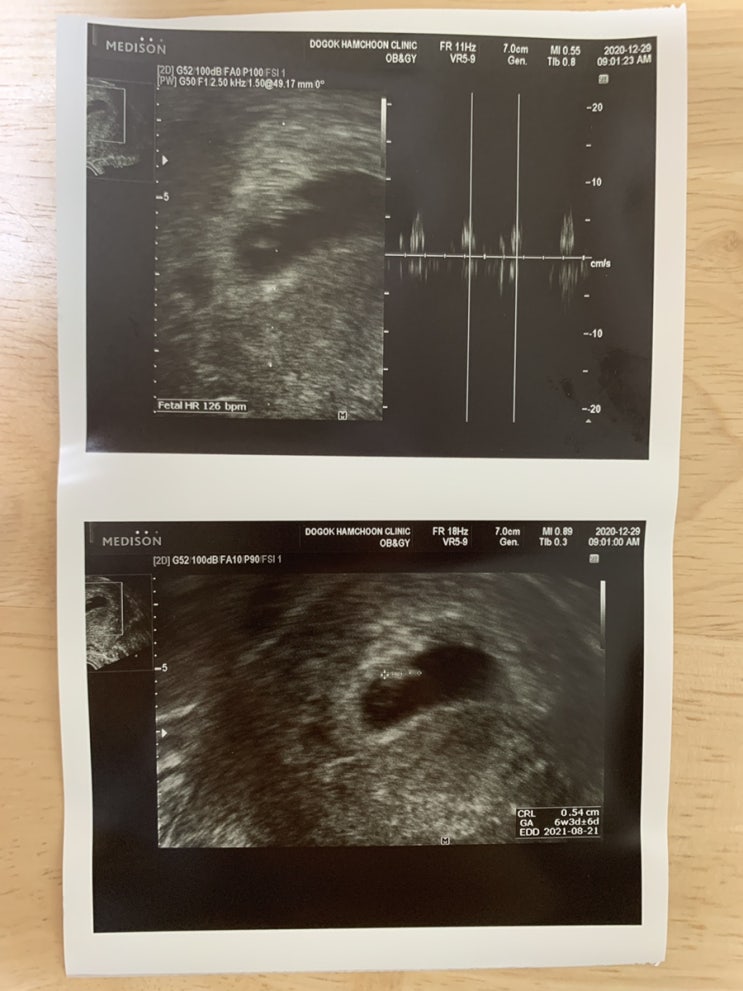

임신 6주차. 산부인과 첫 방문 그리고 태명 꼬복이

— 옛 노트 끄적 내용 가져와 블로그 기록용으로 덧붙이기— 2020.12. 29. 산부인과 방문 얼핏 누워서 아기...